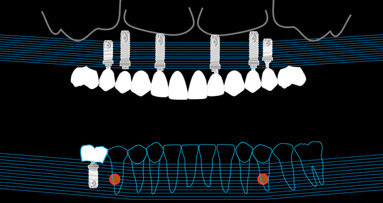

- T0 = durante la prima seduta al paziente è stato fatto firmare il consenso informato e l’informativa sulla privacy per aderire alla sperimentazione, ed è stato rilevato il Test PCR (T0) nella tasca con sondaggio maggiore (Fig. 1);

- T1 = nella seconda seduta è stato rilevato il Test PCR (T1) sullo stesso dente, sette giorni prima della chirurgia implantare; in questa seduta è stata effettuata l’igiene orale professionale mediante l’utilizzo di strumentazione meccanica, cioè un ablatore piezoelettrico in grado di disgregare e decontaminare le tasche mediante cavitazione e tramite strumenti manuali (Fig. 2);

- T2 = nella terza seduta è stato rilevato il Test PCR (T2) sullo stesso dente e sul nuovo impianto un mese dopo il posizionamento degli impianti; in questa seduta sono state compilate: la scheda parodontale iniziale (una volta terminata la quale, sono stati valutati i siti che dovevano essere sottoposti a terapia causale e in base al numero di siti da trattare sono state fissate da 1 a 3 sedute di levigatura radicolare); scheda di raccolta dati (nella quale è stato valutato lo stato parodontale e perimplantare dei pazienti prendendo di riferimento i sei denti campione, denti di Ramfjord);

- T3 = è stato rilevato il Test PCR (T3) sullo stesso dente e sul nuovo impianto, dopo circa tre mesi dall’inserimento della protesi su impianti; in questa seduta sono state effettuate: la scheda parodontale finale (eseguita per valutare l’eventuale miglioramento o peggioramento delle tasche parodontali e perimplantari); la scheda di raccolta dati (eseguita sui denti di Ramfjord per valutare l’eventuale miglioramento o peggioramento degli indici parodontali e perimplantari); la scheda di valutazione iniziale e finale dei singoli denti e impianti sui quali sono stati eseguiti i test microbiologici.